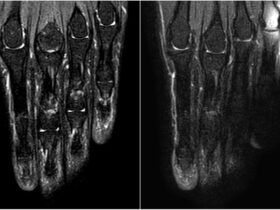

★ほんのひと工夫でここまで変わる!手指MRIポジショニング

★ほんのひと工夫でここまで変わる!手指M...